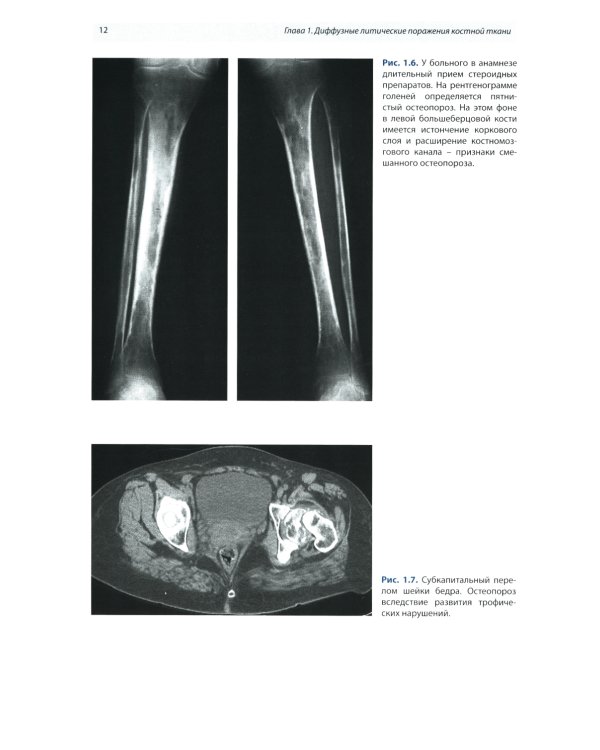

Предлагаемое издание содержит обобщенные сведения по лучевой диагностике патологии костной системы и включает разделы диффузных, воспалительных заболеваний, злокачественных и доброкачественных образований костей. Изложение особенностей каждого заболевания содержит сведения по эпидемиологии, преимущественной локализации в скелете, краткие данные по этиологии и клинической картине поражений. Подробно описаны характерные морфологические изменения и их отображение на обычных рентгенограммах, при КТ и МРТ. освещены вопросы лучевой дифференциальной диагностики. Книга иллюстрирована более чем 200 клиническими наблюдениями с описанием представленных рентгенограмм, КТ- и МРТ-изображений. Издание рекомендуется для практического использования врачами лучевой диагностики, обучения интернов, ординаторов и аспирантов и будет интересно широкому кругу врачей.| Издательство | МЕДпресс-информ |